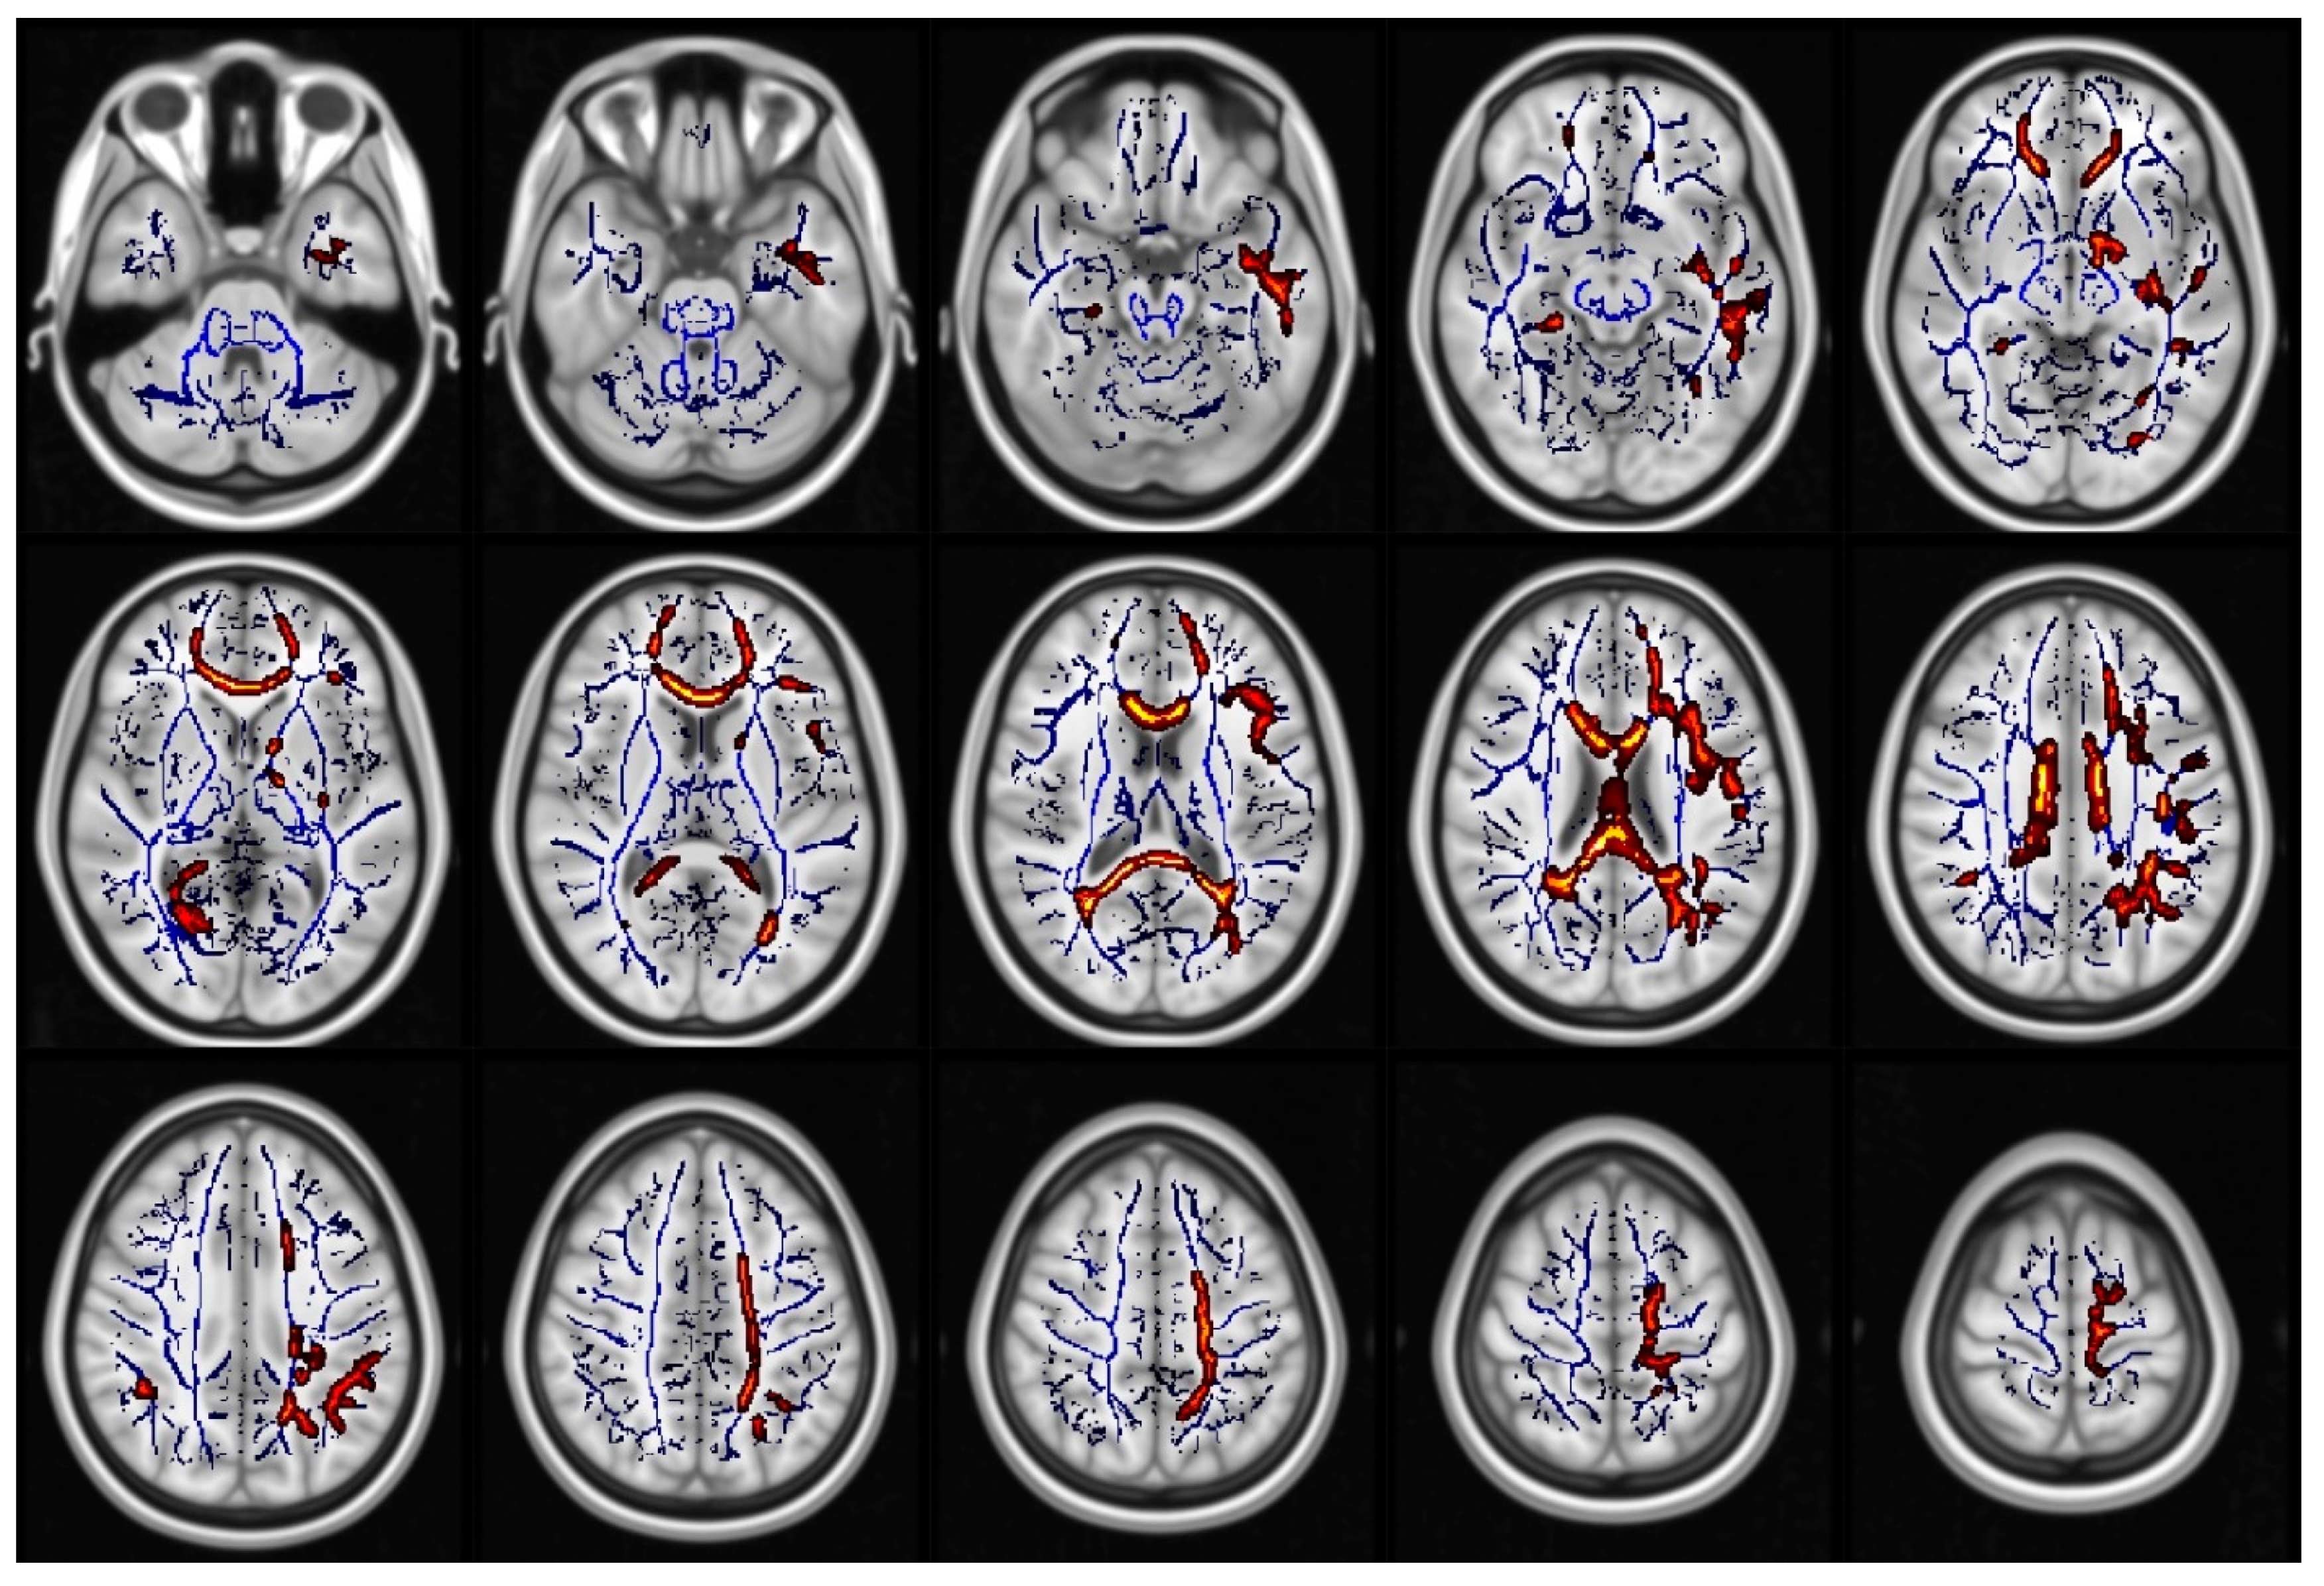

- Smith, S.M.; Jenkinson, M.; Johansen-Berg, H.; Rueckert, D.; Nichols, T.E.; Mackay, C.; E Watkins, K.; Ciccarelli, O.; Cader, M.Z.; Matthews, P.M.; et al. Tract-based spatial statistics: Voxelwise analysis of multi-subject diffusion data. NeuroImage 2006, 31, 1487–1505. [Google Scholar] [CrossRef] [PubMed]

- Smith, S.M.; Nichols, T.E. Threshold-free cluster enhancement: Addressing problems of smoothing, threshold dependence and localisation in cluster inference. NeuroImage 2009, 44, 83–98. [Google Scholar] [CrossRef] [PubMed]